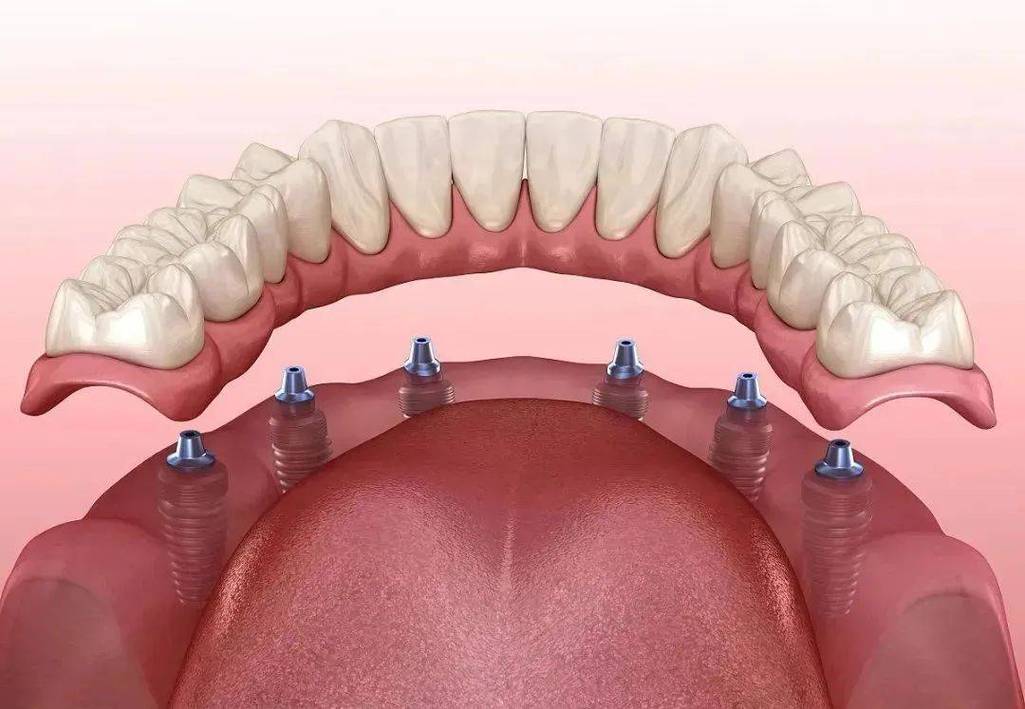

“半口牙即种即用”并非简单的“种完马上用牙”,而是一套结合了数字化精准种植、微创外科技术、即刻负重原理及生物材料学的综合性修复方案,其核心是通过科学的术前规划、高效的手术操作和个性化的修复设计,确保种植体在植入后能够即刻承受一定的咬合力,从而快速恢复口腔功能。

传统种植牙需要3-6个月的骨愈合期(即种植体与牙槽骨结合的“骨整合”过程),期间无法安装牙冠,患者需经历“无牙期”,而即种即用技术通过两大关键突破缩短了这一周期:一是种植体设计优化,采用亲水性表面处理(如SLA活性表面)和锥形锁定结构,增大种植体与骨组织的接触面积,促进成骨细胞附着,加速骨整合;二是即刻负重条件把控,严格筛选适合的患者(如牙槽骨骨量充足、无严重系统性疾病),通过数字化导板精准植入种植体,确保种植初期稳定性(植入扭矩≥35N·cm),同时优化咬合设计,让临时牙冠的咬合力控制在种植体可承受范围内,避免过度负重导致失败。

| 数字化方案设计 | 检查后1-3天 | 基于CBCT数据制作3D打印导板,规划种植体数量(半口通常4-6颗)、位置、角度,模拟咬合关系。 |

| 手术植入 | 治疗当天 | 局部麻醉下,通过导板微创植入种植体,植入扭矩达35N·cm以上,安装临时基台和牙冠(树脂或临时冠材料)。 |